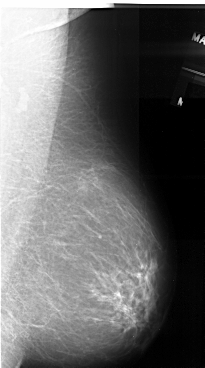

A_1055_1.LEFT_MLO

LEFT_MLO LINES 5521 PIXELS_PER_LINE 3121 BITS_PER_PIXEL 16 RESOLUTION 42 OVERLAY